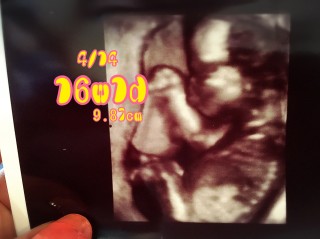

病院でのエコーではわからなかったけど 帰ってUSBの動画を見て見たら ぐっすり寝てる(笑)寝顔がパパそっくり! まだ性別はわからないねと言われたので 6ヶ月検診までお預け。 大きさはだいたい9cm 順調ということで安心しました(*^^*)

前回の健診から1ヶ月たってて心配だったけど元気に動いてくれてちゃんと成長してくれててひと安心。 4D撮ってもらいました!! まだまだ骨だらけですがこれからしっかり育ってくれます様に。